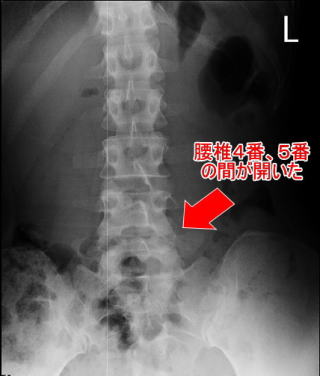

施術前 施術前の腰椎

施術前:腰椎が右に傾き、4番と5番の間が狭くなり椎間板が飛び出している

施術後:腰椎が真っ直ぐになり、4番と5番の間が広がり椎間板も凹み、腰痛が消失

※副院長自身の椎間板ヘルニアの写真です

Afterは最初の施術から4ヶ月後の写真です

※すべての方に同様の変化を保証するものではありません